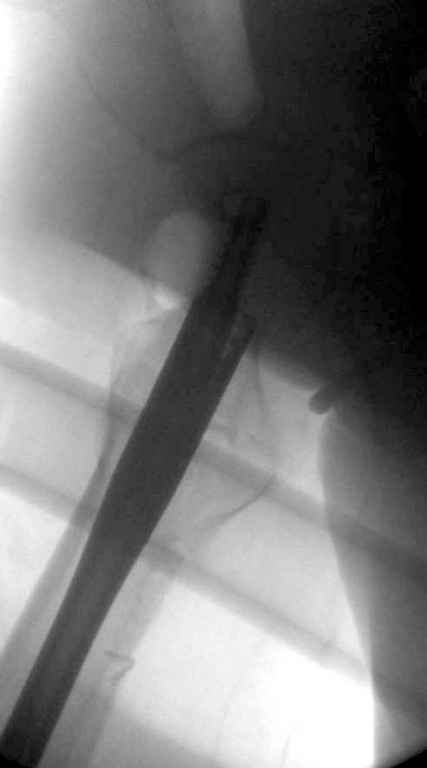

В приложении похожий пример, к счастью, пациентка появилась не после, а "за полчаса" до протрузии. Пересинтезировали с исправлением ошибок.

Вашему вниманию представляется похожий случай, пациентке 70, осложнился в течение одного месяца после операции. Ревизия с заменой сустава, кабельная фиксация на трохантер. При установке в дистальном диафизе обнаружен тонкий кортикальный слой и сделана профилактика от возможного перелома аллографтом.